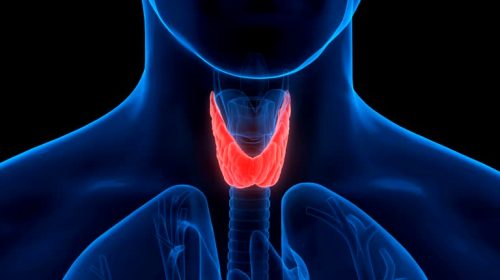

Endocrine System

Endocrine system disorders, like diabetes and thyroid imbalances, affect hormone regulation. Treatment typically involves medication and lifestyle changes.